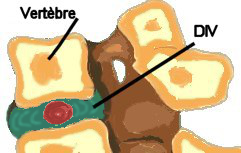

Le disque intervertébral (DIV) est constitué de 2 parties :

- l'anneau fibreux (annulus

fibrosus), fibrocartilage et fibres de collagène

disposées en couches concentriques dont l'orientation des fibres

change d'une couche à l'autre. La périphérie du disque est fixée aux

corps vertébraux par du cartilage hyalin, il est maintenu entre les

vertèbres grâce aux lig. vertébraux communs.

- le noyau (nucléus pulposus)

gélatineux. Riche en eau, il est déformable mais incompressible :

qualité qu'il perd en vieillissant. Son rôle est d'amortir et de

répartir les contraintes et les pressions. Il est situé d'autant plus

en ARR par rapport au centre que l'on descend dans la colonne

vertébrale.